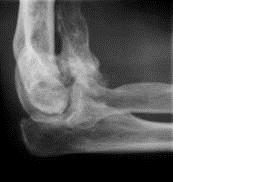

Elbow Fracture

Our centre provides different alternatives to help patient with elbow fractures, like radial head, locking plate system, etc… Complex elbow fractures are challenging. We employ the techniques available to reconstruct both acute as well as chronic injuries.

Before surgery